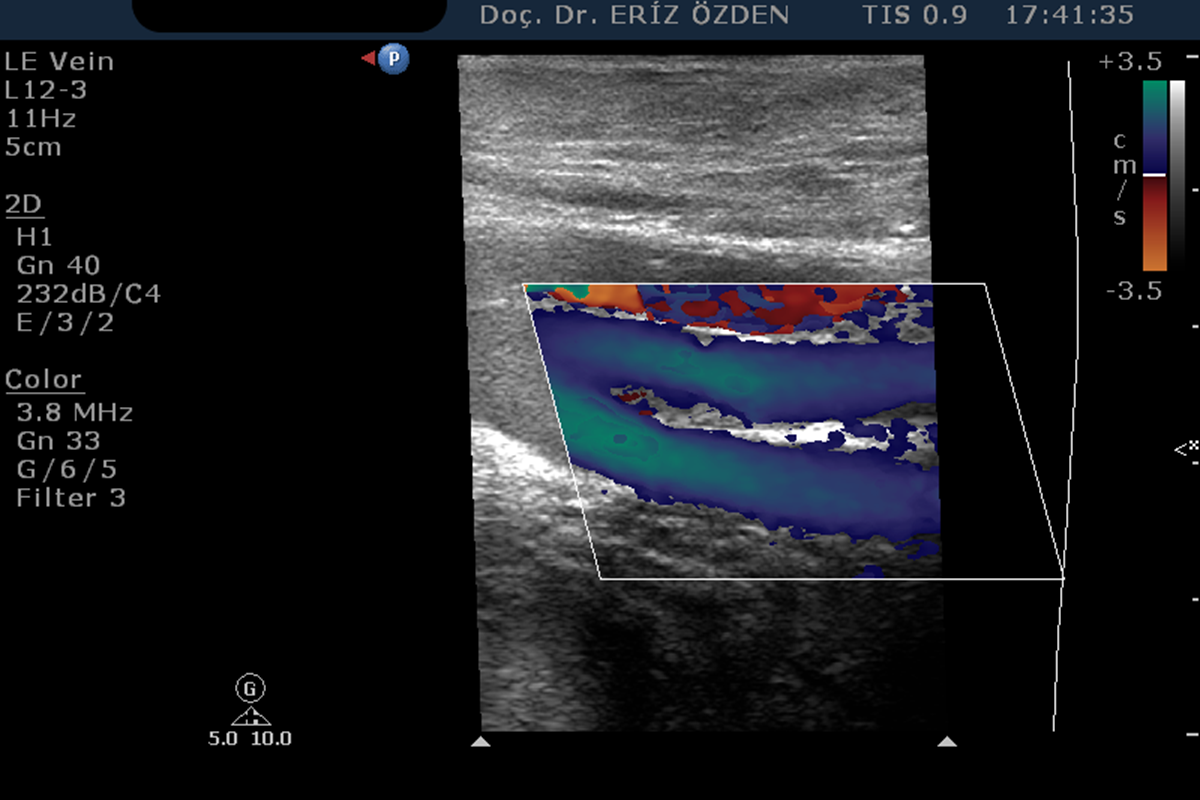

Bacak Venöz Doppler Nasıl Yapılır? Ultrasonografi cihazı Renkli Doppler özelliğine sahipse, damarların içindeki kan akımını renkli olarak görmek mümkündür. Renkli Doppler Ultrason adı verilen bu yöntem sayesinde damarlardaki daralmalar, pıhtılar ve tıkanıklar saptanır. Kan akım hızına yönelik ölçümler yapılır. Bacak atar ve toplar damarlarındaki problemlerde Renkli Doppler çok sık kullanılır. Toplardamarların içindeki kan akımı renkli olarak görülür. Kan akımının yönü, miktarı, damarlada geriye kaçış olup ulmadığı ve en önemlisi toplardamarlar içindeki pıhtılar tespit edilir. İnceleme önce hasta sırt üstü yatırılarak başlar. Kasıktan başlayarak ayak bileğine kadar tüm toplardamarlar incelenir. Bunun için hastanın bacağına jel sürülür ve ultrason cihazının başlığı cildinin üzerine dokundurulur. İnceleme hiç acı vermez. Renkli doppler yöntemiyle bacak içindeki toplardamarlar renkli olarak görülür. Kasıltan ayak bileğine kadar bacakta bulunan çok sayıda toplardamarın hepsi, ayrı ayrı, santim santim takip edilerek, içindeki kan akımı, pıhtı varlığı, damar yetmezliği açısından incelenir. Devamında hasta yüzüstü yatırılarak diz ve bacak arkasında yer alan toplardamarlar incelenir. Ardından hasta dik pozisyona getirilir. Bu aşamada, hasta dik duruken, yer çekimi ile damarlarda yetmezlik ortaya çıkıp çıkmadığına bakılır.

Bacak Venöz Renkli Doppler Tetkiki Neden Yapılır? Venöz Renkli Doppler tetkiki, bacak toplardamarlarındaki varislerin, yetmezliklerin ve pıhtı oluşumlarının araştırılmasında kullanılır. Uzun süre ayakta durarak çalışanlarda, ileri yaşlardaki kişilerde, çoğunlukla da bilinmeyen nedenlerle bacak toplardamarlarında yetmezlik olabilir. Normalde toplardamarlardaki kirli kan, devamlı olarak yukarı, yani kalbe doğru akar. Hastanın ıkınması, öksürmesi, uzun süre ayakta kalması gibi durumlarda kan geriye doğru akmamalıdır. Damar içindeki ince kapakçıklar geriye akımı önler. Kanın geriye doğru kaçış göstermesine reflü akım denir. Bu durum venöz yetmezlik olarak adlandırılır ve bacaklarda şişme ya da varislerin oluşmasına neden olabilir. Hangi damarlarda, hangi derecede yetmezlik olduğu Venöz Renkli Doppler Ultrasonografi tetkiki ile anlaşılır.